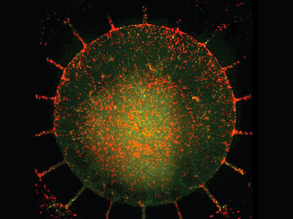

Frozen Herpes